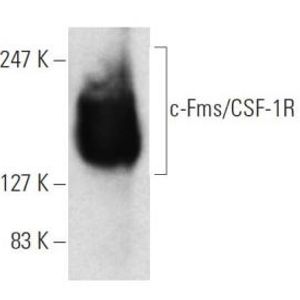

JUL 28, 2025Drug Discovery & DevelopmentOne lab technique that has been around since what feels like the dawn of time is Western blotting, and it doesn&r ...